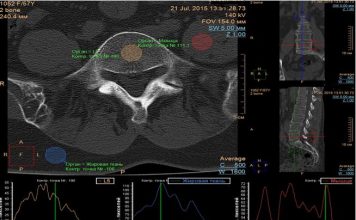

Диагностика заболеваний поясничного отдела позвоночника при помощи компьютерной томографии (КТ) в Украине

Поясничный отдел позвоночника - это нижняя часть позвоночного столба, расположенная в области поясницы человеческого тела. Он состоит из пяти позвонков, которые отвечают за поддержку...